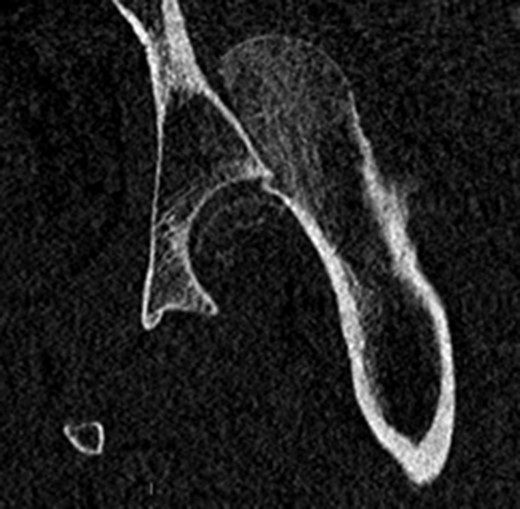

In addition to the bony injury, labral detachment and tearing were noted (later repaired with suture anchors). The femoral head was comminuted and had areas of missing articular cartilage especially posteriorly and superiorly with a 1 × 1 cm2 area of full thickness cartilage loss (Fig. 4). The weight-bearing zone was relatively unaffected. The ligamentum teres had to be released to allow fracture reduction and fixation with four headless compression screws (Fig. 5). A good fixation was achieved. Microfracture was performed on the articular cartilage defect. The femoral head, fracture fragment and microfracture site were bleeding and appeared viable.

Intraoperative view of the femoral head after fixation with headless compression screws.